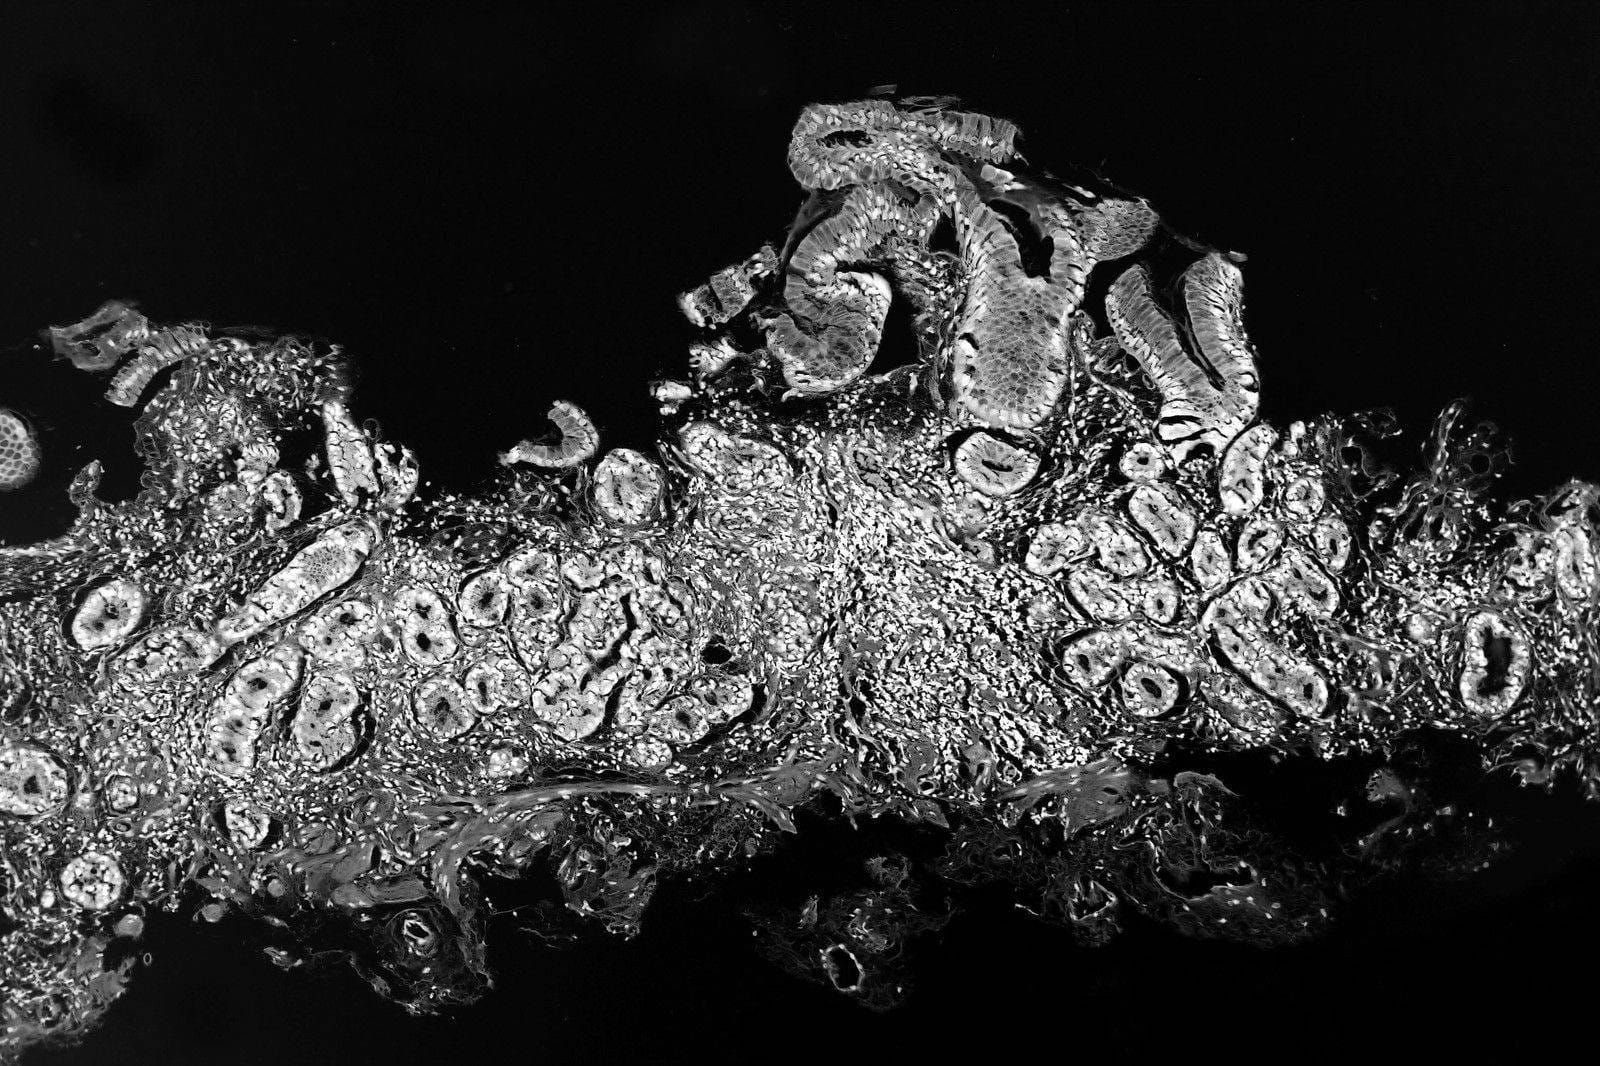

Cover photo "Autoimmune atrophic gastritis (H&E)" by CoRus13 is licensed under CC BY-SA 4.0